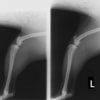

■ 症例20 ポメラニアン 8ヶ月 1.8kg

左右膝蓋骨脱臼 グレードⅢ

2ヶ月前から間欠的跛行が認められ、両膝の膝蓋骨脱臼整復術を行った。

手技は縫工筋及び内側広筋の解放、脛骨粗面の外側転位、滑車ブロック形造溝術、内外側関節包の縫縮を選択し実施した。

右側の膝蓋骨脱臼は上記手技で整復されたものの、左側はそれのみでは膝蓋骨が浮く様子が認められた。その為、PDS縫合糸にて膝蓋靱帯を1糸のみ縫合し、靱帯の縫縮を行った。

膝蓋骨脱臼は膝関節における膝蓋骨の内外側の脱臼と定義されるが、時として単純な内外の脱臼ではなく、膝蓋骨が大きく前方に浮き上がるように脱臼する場合がある。特にトイプードルやポメラニアンといった犬種に多く認められる。

内側脱臼に加えて前方への浮き上がりを矯正する為に、従来より脛骨粗面転移により膝蓋靭帯を外方と下方に引っ張り、固定する方法を選択する。膝蓋骨の前方への浮き上がりが軽度の場合は、従来法ではなく関節包の縫縮で対応していた。しかし、一部の症例で膝蓋骨の動きが悪くなり伸展機構が円滑に機能せずロボット様歩行になるケースがあった。

その為、膝蓋靭帯自体を縫縮する方法を採用した。この方法により、膝関節の伸展機構を妨げず膝蓋骨の軽度の浮きを矯正することが可能となった。

本症例の経過は良好である